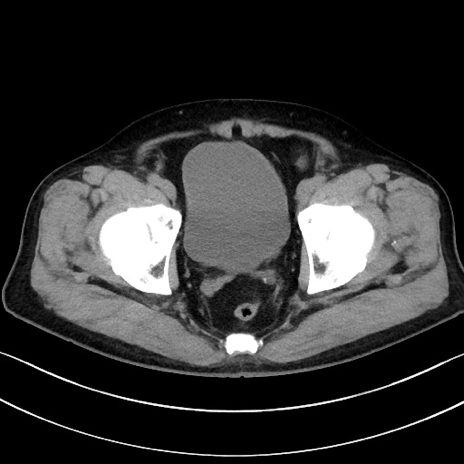

症例15(横断像)

【症例】70歳代男性

【主訴】腹痛

【現病歴】今朝から腹痛あり。全体的に痛い。特に左上の方。排ガスが今日はない。冷や汗が出る。

【既往歴】直腸癌術後

【身体所見】左側腹部〜上腹部に圧痛あり。腹膜刺激症状明らかなではない。軽度反跳痛。左下腹部に術後瘢痕あり。

【データ】WBC 7700、CRP 0.02